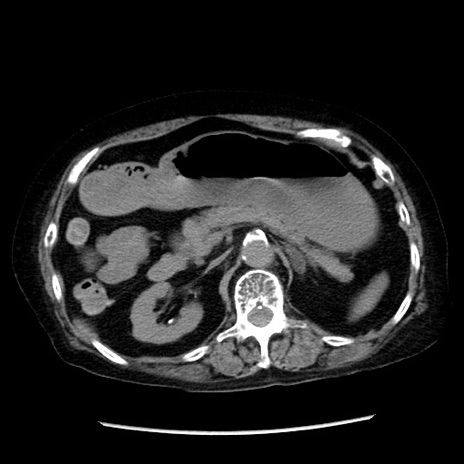

症例14(横断像)

【症例】 90歳代女性

【主訴】 腹痛・嘔吐

【現病歴】今朝から左側腹部痛を認めた。 経過観察していたが、嘔吐を認めたため来院。

【既往歴】 子宮癌術後

【身体所見】 意識清明、BP 127/54mmHg、P 98bpm Sp02 95%(RA)、BT 35.8°C、腹部平坦・軟腸ぜん動音聴取良好、右下腹部圧痛(+) 反跳痛なし

【データ】WBC 9800、CRP 0.46